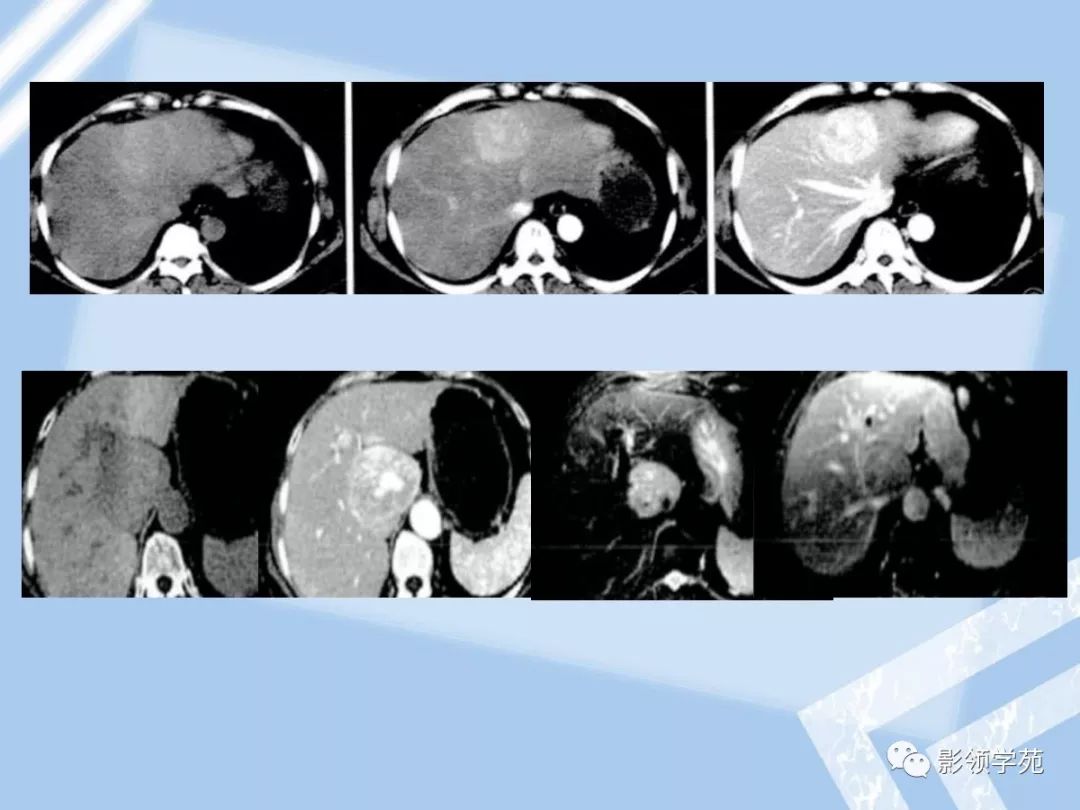

22种肝脏少见及不典型肿瘤的影像表现

图片尺寸1080x810